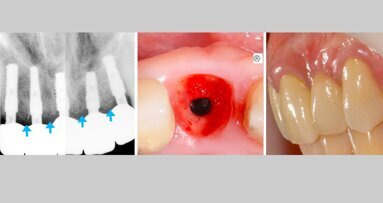

Dentro de estas nuevas técnicas, consideradas las avanzadas en la implantología oral, está la elevación sinusal con sus diferentes variantes. Todas ellas predecibles y realizables, con unos conocimientos y un entrenamiento adecuado por los profesionales de la salud bucal, sin que ello exima de los riesgos y complicaciones de toda técnica oral y con un grado de complejidad creciente.

Este libro está distribuido en tres grupos y numerosos capítulos independientes entre sí, pero con el nexo de la lógica temporal de la realización de esta técnica. Desde la planificación de la rehabilitación, pasando por las diferentes opciones de la técnica y las complicaciones, intentando condensar los conocimientos adecuados, o al menos la mayoría de ellos, para obtener una guía de realización del proceso de la elevación sinusal en todos sus ámbitos.

Es un libro de consulta y de aprendizaje, ya que a los profesionales se nos crean numerosas incertidumbres en nuestra práctica diaria habitual, surgiendo dudas en algunos aspectos metodológicos cuando se plantea realizar algún proceso. Y más si es de un cierto tipo de complejidad.